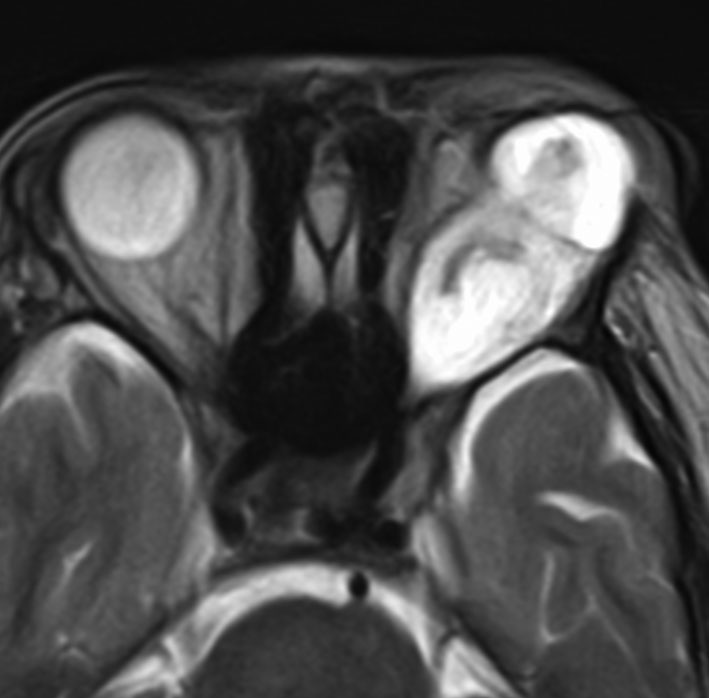

視索に限局する毛様細胞性星細胞腫

左の視索の内部から発生したもので,これも単神経・視神経膠腫と同様によくみるものです。左の画像で視神経交叉が全く侵されていないのがわかります。

単視神経膠腫は全摘出できるのですが,このタイプは外側膝状体へ及ぶので完全摘出ができません。部分摘出と定位放射線治療が適応となります。